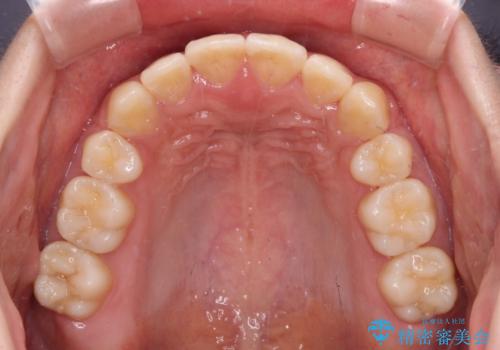

短期間で口元の突出感を改善 ワイヤー装置での抜歯矯正

上下左右4本抜歯する場合には、通常2年から2年半ほどの期間を要しますが、僅か1年半で終了することができました。